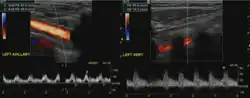

Doppler ultrasound of subclavian steal phenomenon